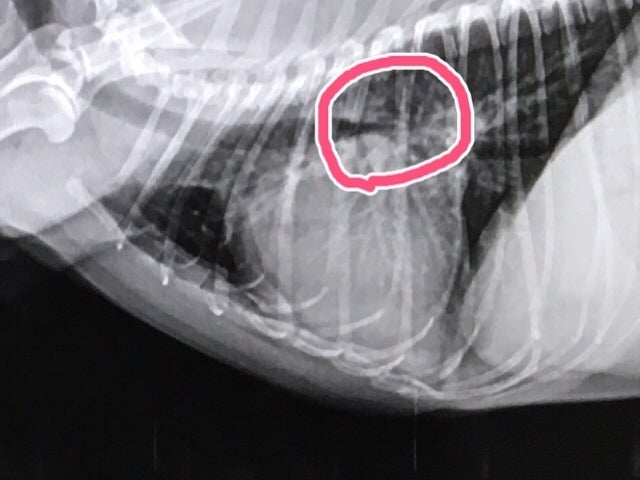

こちらが手術後の心臓になります。

気管を押し上げていた心臓が小さくなり、潰れていた気管が通りました。

この大きな違いを写真で見せていただいた時、感動致しました。